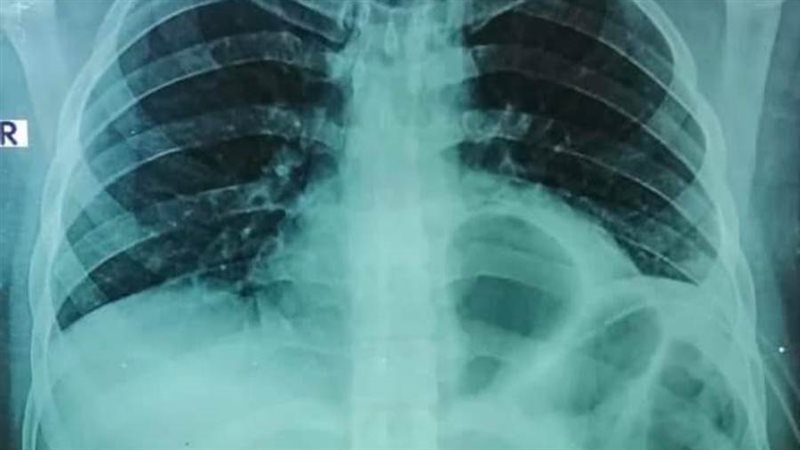

وكشف بيان مستشفى بنها الجامعي، أنه حضر للمستشفى شاب يعاني من نزيف وتجمع دموي بالغشاء البللوري المحيط بالرئة اليسري، وتم تركيب درنفة صدرية لتفريغ الدم المتجمع.

أضاف البيان، أنه عقب إجراء الأشعة المبدئية، تبين وجود اشتباه وجود أجزاء من المعدة والأمعاء بالقفص الصدري فجري تفريغ الدم المتجمع، مما استلزم تحضير المريض لجراحة استكشاف صدري عاجل، حيث تبين أن المطواة أدت الي فتحة دخول من القفص الصدري تحت الرئة اليسري مخترقة الحجاب الحاجز من الأمام ثم اخترقت تجويف البطن وأدت إلى فتحة خروج في الحجاب الحاجز من الخلف بجانب الشريان الأورطي ب ٢ سم فقط في تجويف الصدر، إلا أن الاختراق الخطير لم يؤد إلى جرح الأمعاء أو المعدة أو الكبد أو الرئة أو الشريان الرئيسي، برغم أن اتجاه المطواة في وسط كل هذه الأعضاء الخطيرة.